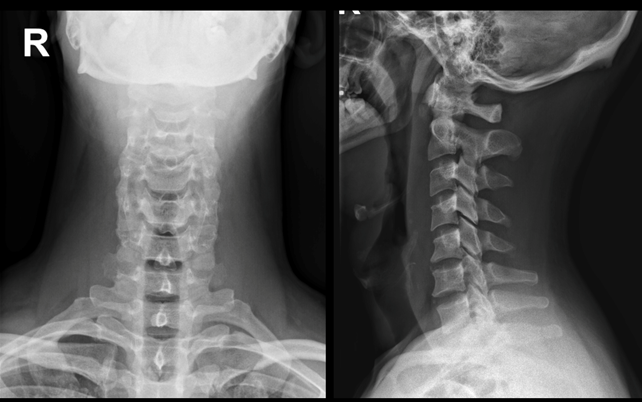

Se realiza radiografía de columna cervical, enfoques de frente y perfil, visualizándose aumento del espacio prevertebral, y constatándose de forma sutil una calcificación en la región anterior de C1-C2.

Figura 2: Radiografía columna cervical de nuestro paciente. A) Enfoque radiográfico anteroposterior, que impresiona normal. B) Enfoque radiográfico lateral en la que se observa un espacio prevertebral levemente aumentado en sector cervical alto (Medición normal de 7mm a nivel de C3 y 3cm a nivel de C7).